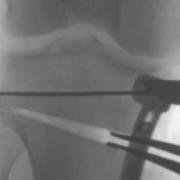

Laminar spreaders open the wedge of a high tibial osteotomy, and then the bone is held in the new position with a plate and screws until new bone fills the gap.

Planning software with full-length weight-bearing X-rays allows pre-operative calculation of the required amount of wedge correction in the tibia in mm.